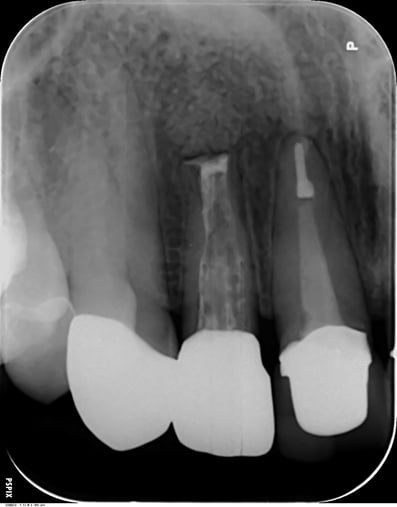

歯根端切除術 Apicopectomy

下顎前歯 root endo sealing

術後4年。